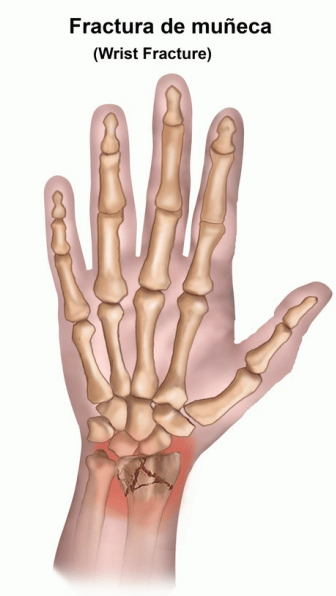

Una fractura de radio distal es una fisura o rotura en la parte más distal del hueso del radio, cerca de la muñeca. La fractura puede variar desde una pequeña fisura en el hueso hasta una fractura compleja donde el hueso se rompe en varios pedazos. Las fracturas de radio distal son más comunes que otras fracturas de la muñeca.

Deformidad visible, donde la muñeca puede verse torcida o fuera de lugar.